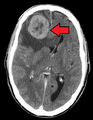

- الدماغ: الأعراض العصبية مثل الصداع، التشنجات، والدوار